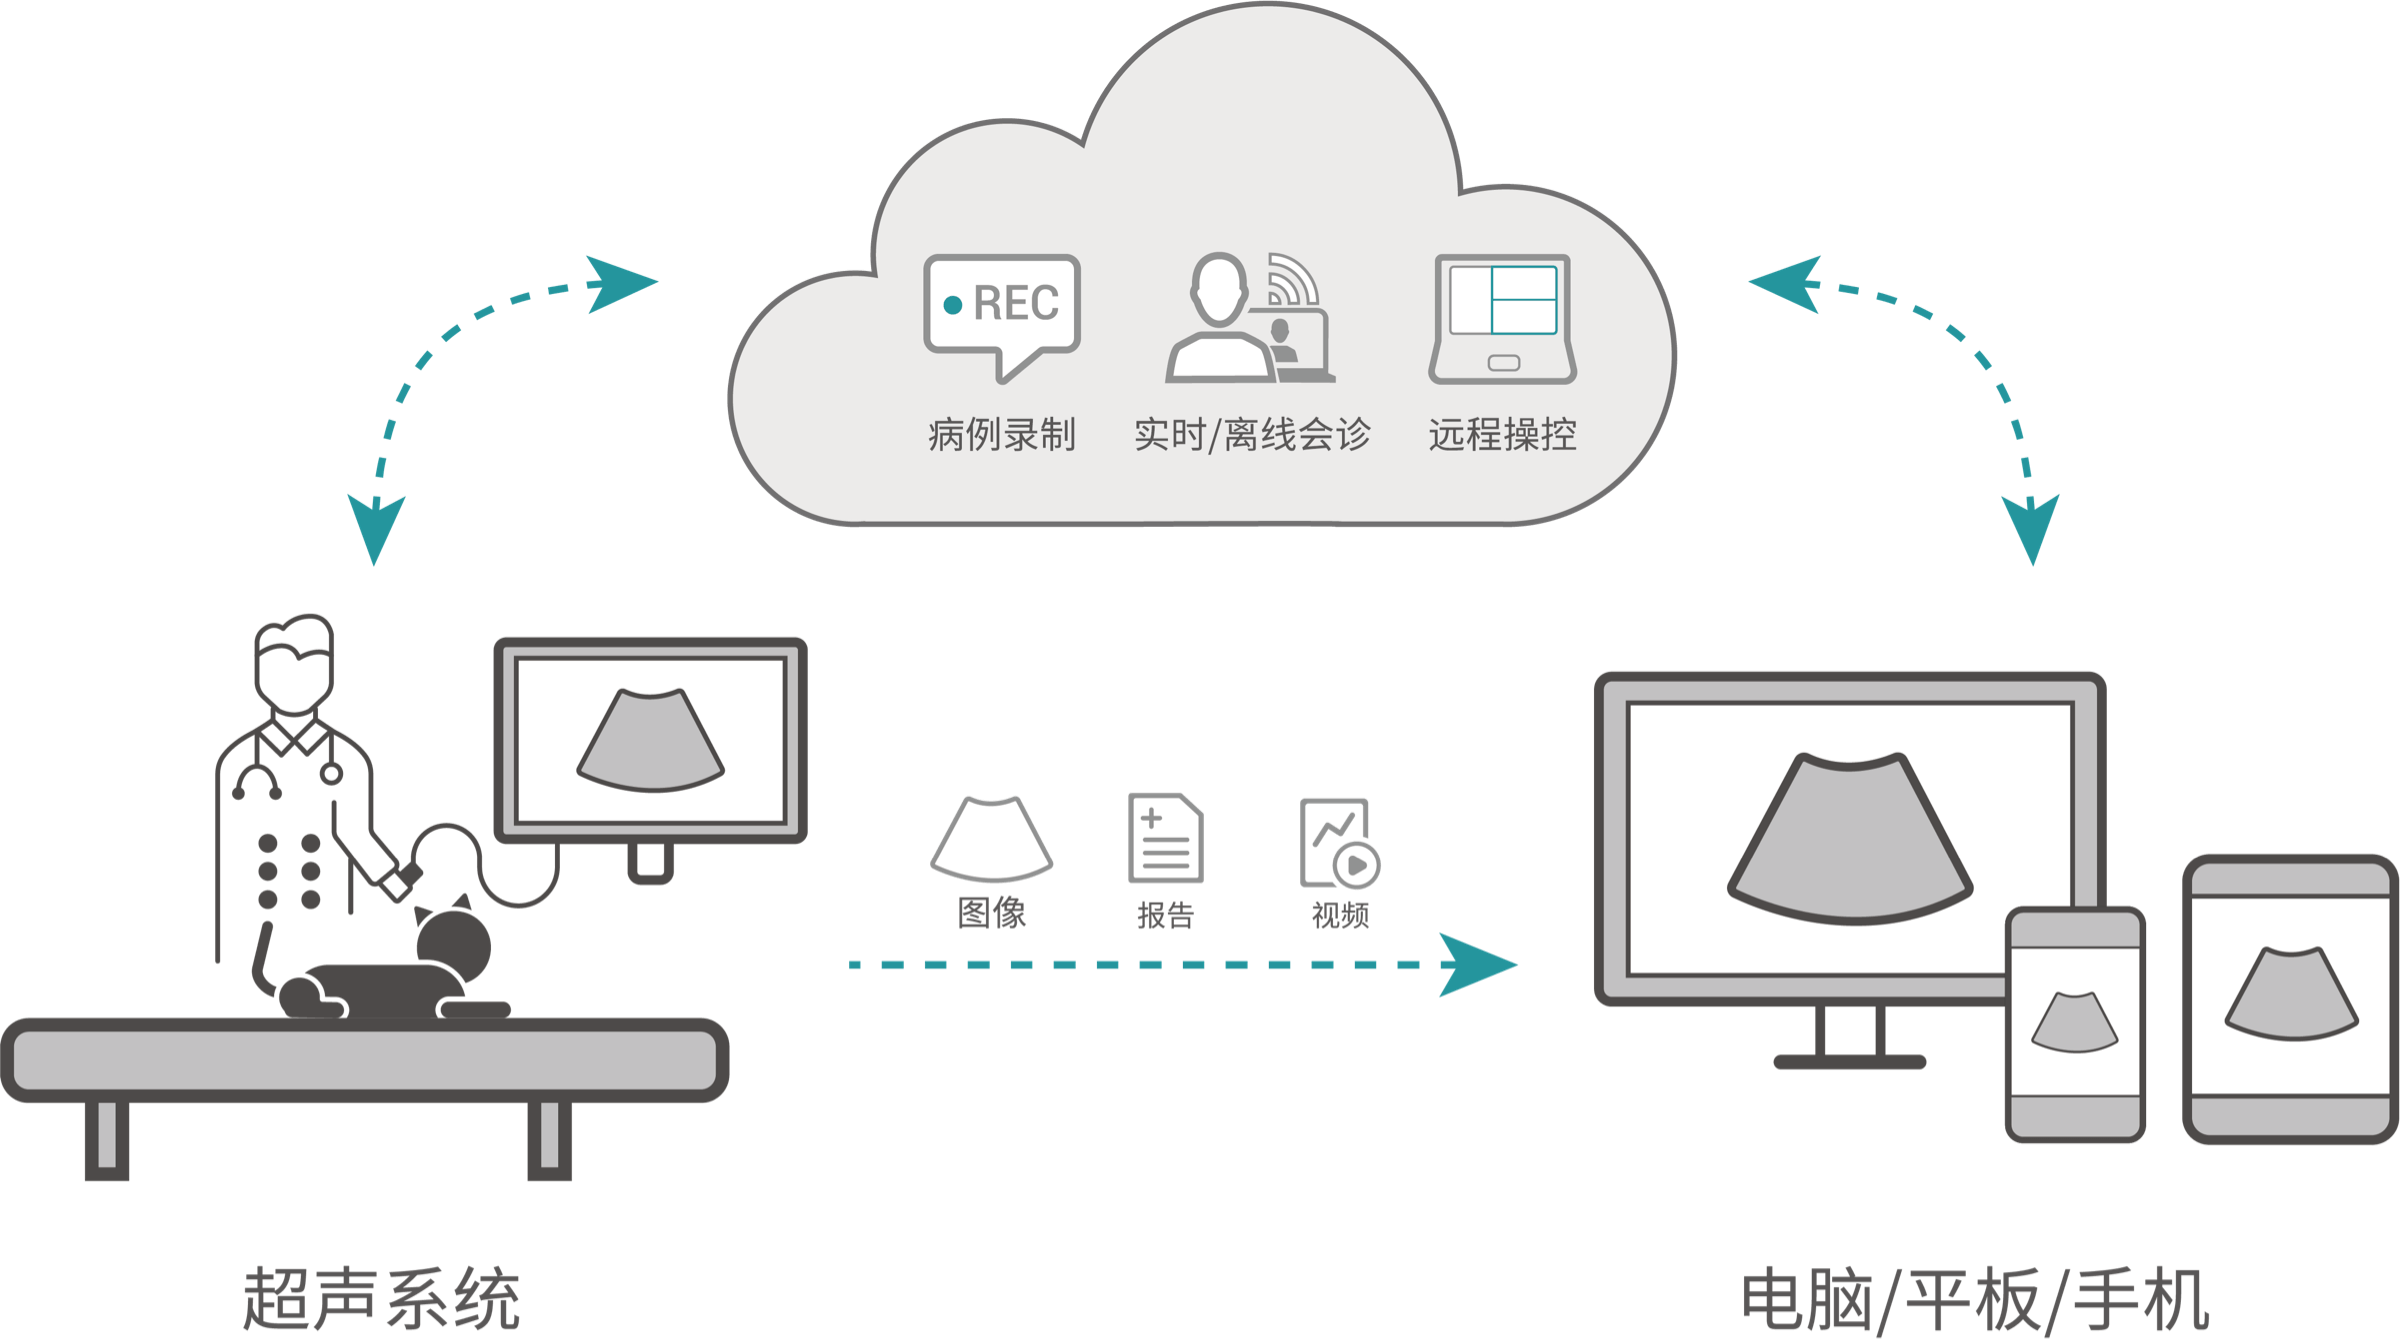

ProPet 60 作为一款高端台式动物超声设备,为动物医生的日常诊断提供了一系列贴合动物临床需求、解决临床实际问题的高级成像功能。凭借全系列高清探头,满足医生对腹部、心脏、生殖、浅表、肌骨等成像的所有需求,切实帮助您提升检查效率,提高诊断信心。

动物是人类最亲密的朋友和最值得信赖的伙伴。DB中国旗舰官方网站也一直致力于探索动物专用的超声影像解决方案。 全新推出的ProPet系列,是DB中国旗舰官方网站在动物超声影像智能化、专业化、精准化的一次跨越式革新。动物不能用言语来表述自己的不适,通过超声影像,ProPet系列搭建了动物医生与不同物种沟通的“桥梁”,为动物医生注入了“治愈之力”。